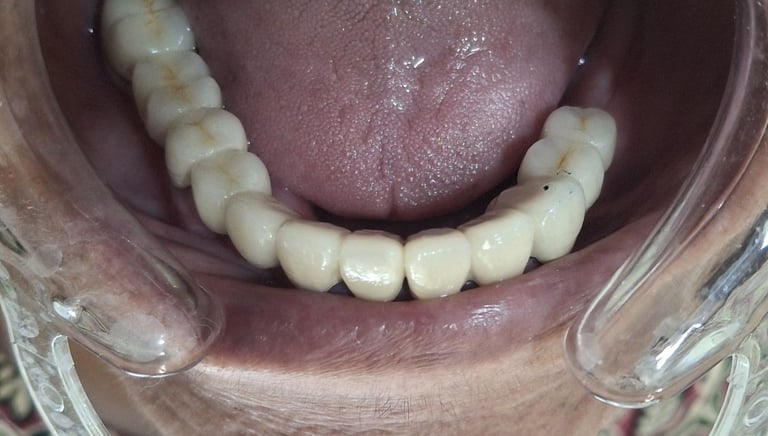

Professional Teeth Cleaning in Shyamal, Ahmedabad

Gentle, properly performed and tailored teeth cleaning for each person giving you comfort, safety and visible results. People from Shyamal and nearby areas of Ahmedabad visit our clinic for comfortable and very effective teeth cleaning.

All images shown here are real teeth cleaning cases treated at our clinic with patient consent.

Professional teeth cleaning helps remove plaque, tarter, and surface stains that regular at home brushing can not.

At Shree Dental Care, teeth cleaning is performed gently with focus on patient experience, comfort and long term oral health.

If you are looking for gentle teeth cleaning in Shyamal, Ahmedabad, you can book an appointment with our clinic.